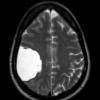

10A1 Ulegyria (Case 10) FLAIR 2

10A2 Ulegyria (Case 10) FLAIR 3

10A3 Ulegyria (Case 10) FLAIR 4

10A4 Ulegyria (Case 10) FLAIR 5

10A5 Ulegyria (Case 10) T2W 2

10A6 Ulegyria (Case 10) T2